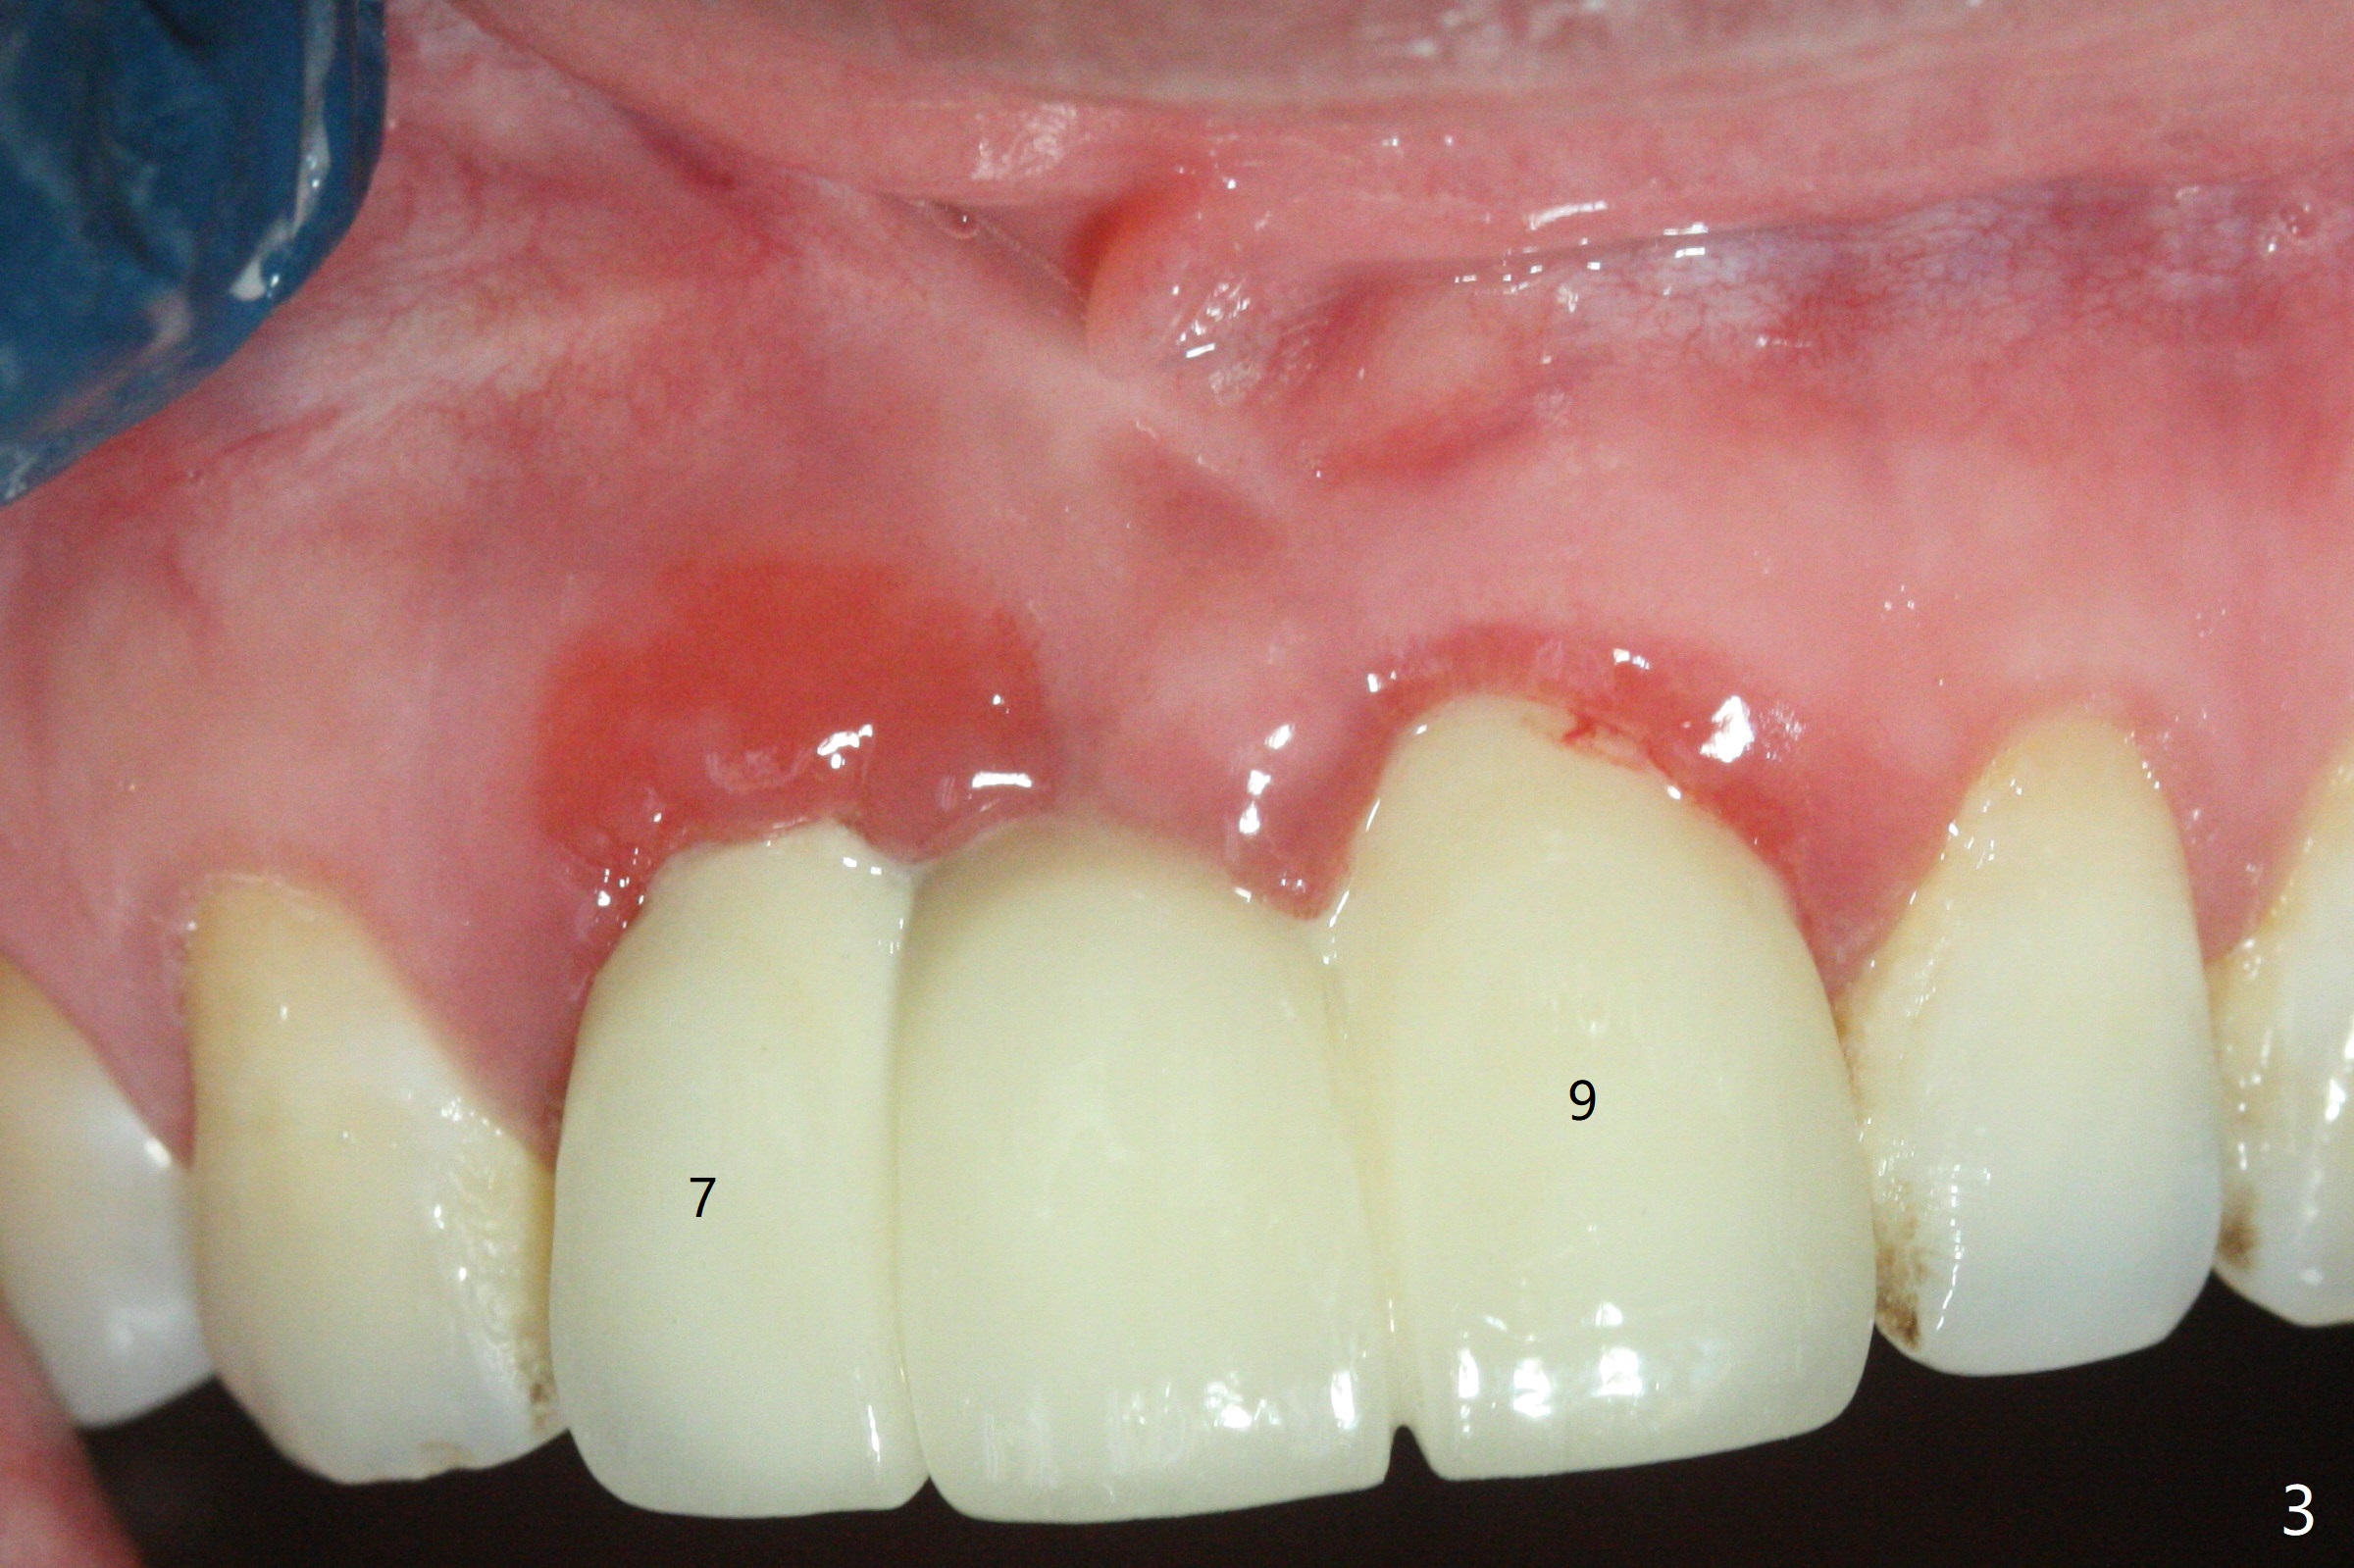

A 34-year-old woman requests fixing the failed anterior FPD (Fig.1). The edentulous alveolus looks thin; 1-piece implant may be indicated at most. A regular narrow 2-piece implant will be placed at the lateral incisor (Fig.2). CT is necessary for treatment planning. Impression has been taken for stent fabrication. 34岁女,一年半前来诊所(图一,二(侧切牙种植,做悬臂桥,暂时保留左上1牙冠)),希望修复右上门牙桥。现在终于要求立即做,基牙处牙龈红肿 (图三(今天做深洗)),牙桥颊侧移位(图四),侧切牙(7号牙)牙槽嵴也不是很宽,植入3.5毫米植体(两段式, IBS)还勉强(图五)。为了简化,避免悬臂桥,我还想在中切牙(8号牙)无牙处植入一段式2.5毫米植体(图六),适当做些牙槽嵴劈开(图六右上图:红线; from IBS cassette)。这周末徒手植入,她离开时应该有固定临时修复物。

一段式植体似乎不美观,其实它适用于近中远中空间狭窄地方,如这个病例,而两段式植体显得太粗,没有空间形成牙龈乳头,况且容易以后导致植牙周围炎。即刻临时牙冠手术第一天就起到美观作用,术后三四个月中反复调整,为永久性牙冠奠定基础。以下手术步骤就是为了这个目的。在中切牙之间切断牙桥,为右上1狭窄牙槽嵴拍摄照片(颊侧,咬合面观),切口,铬羊肠缝线牵拉,外科车针去除尖端牙槽嵴直到后者宽度达到~ 3毫米,使用1.2毫米一段式钻头,8 毫米,插入一个已经折断同样大小车针作为定位;拔除侧切牙,拍摄各式各样刮匙和肉芽组织去除器械,用1.6毫米钻头在腭侧骨板钻洞,深度9毫米,拍摄术中第一张根尖片;在中切牙处使用片状骨凿稍做骨扩张,必要时旋转式扩大器,之后完成牙槽嵴下植体放置,侧切牙牙槽窝以及中切牙术野插入无絮棉布,做必要基台制备,使用成品临时牙冠制作两个分开牙冠,确保牙龈下边缘,取出棉布,植骨,放置PRF膜,插入临时牙冠,尤其是中切牙牙冠和骨粉将改善颊侧,腭侧(与图四箭头对比)饱满度,最后缝合,调整咬合。7,8号牙骨质密度分别为700和 500单位(图七,八)。